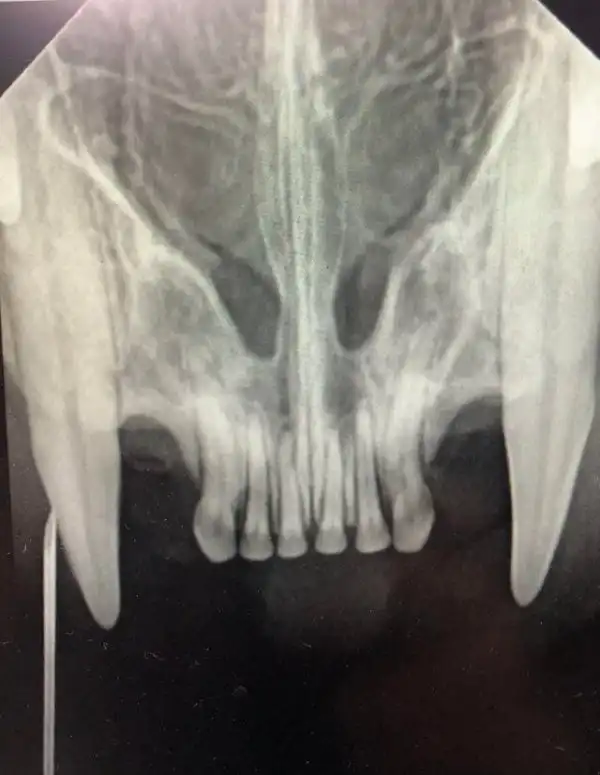

Рентгенограмма верхних резцов и клыков у кошки